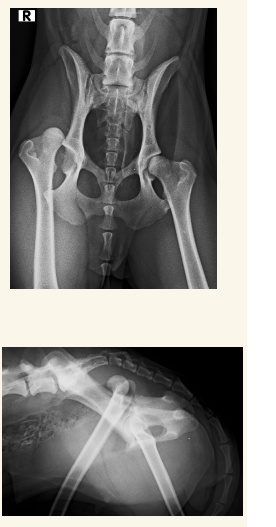

Luxación Coxo-femoral

- Por traumatismo, a veces leve si existe Displasia. Suele aparecer con fracturas de pelvis, uni o bilateral

- Normalmente cráneo-dorsal, aunque puede ser dorsal, ventral, caudal (rara) o intrapélvica

- Mejor 2 proyecciones pero en VD se ve mejor (ilion desplazado, mayor tamaño articular, perdida de contorno liso)

- Tambien hay luxacion sacro iliaca.

- Hay que ver la direccion de la luxacion. La mas frecuente es craneo-dorsal pero hay mas.